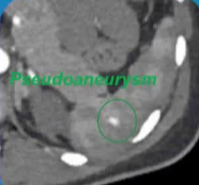

伴有血管损伤的患者 |

特定受损血管的选择(超选择行) |

选择性栓塞 |